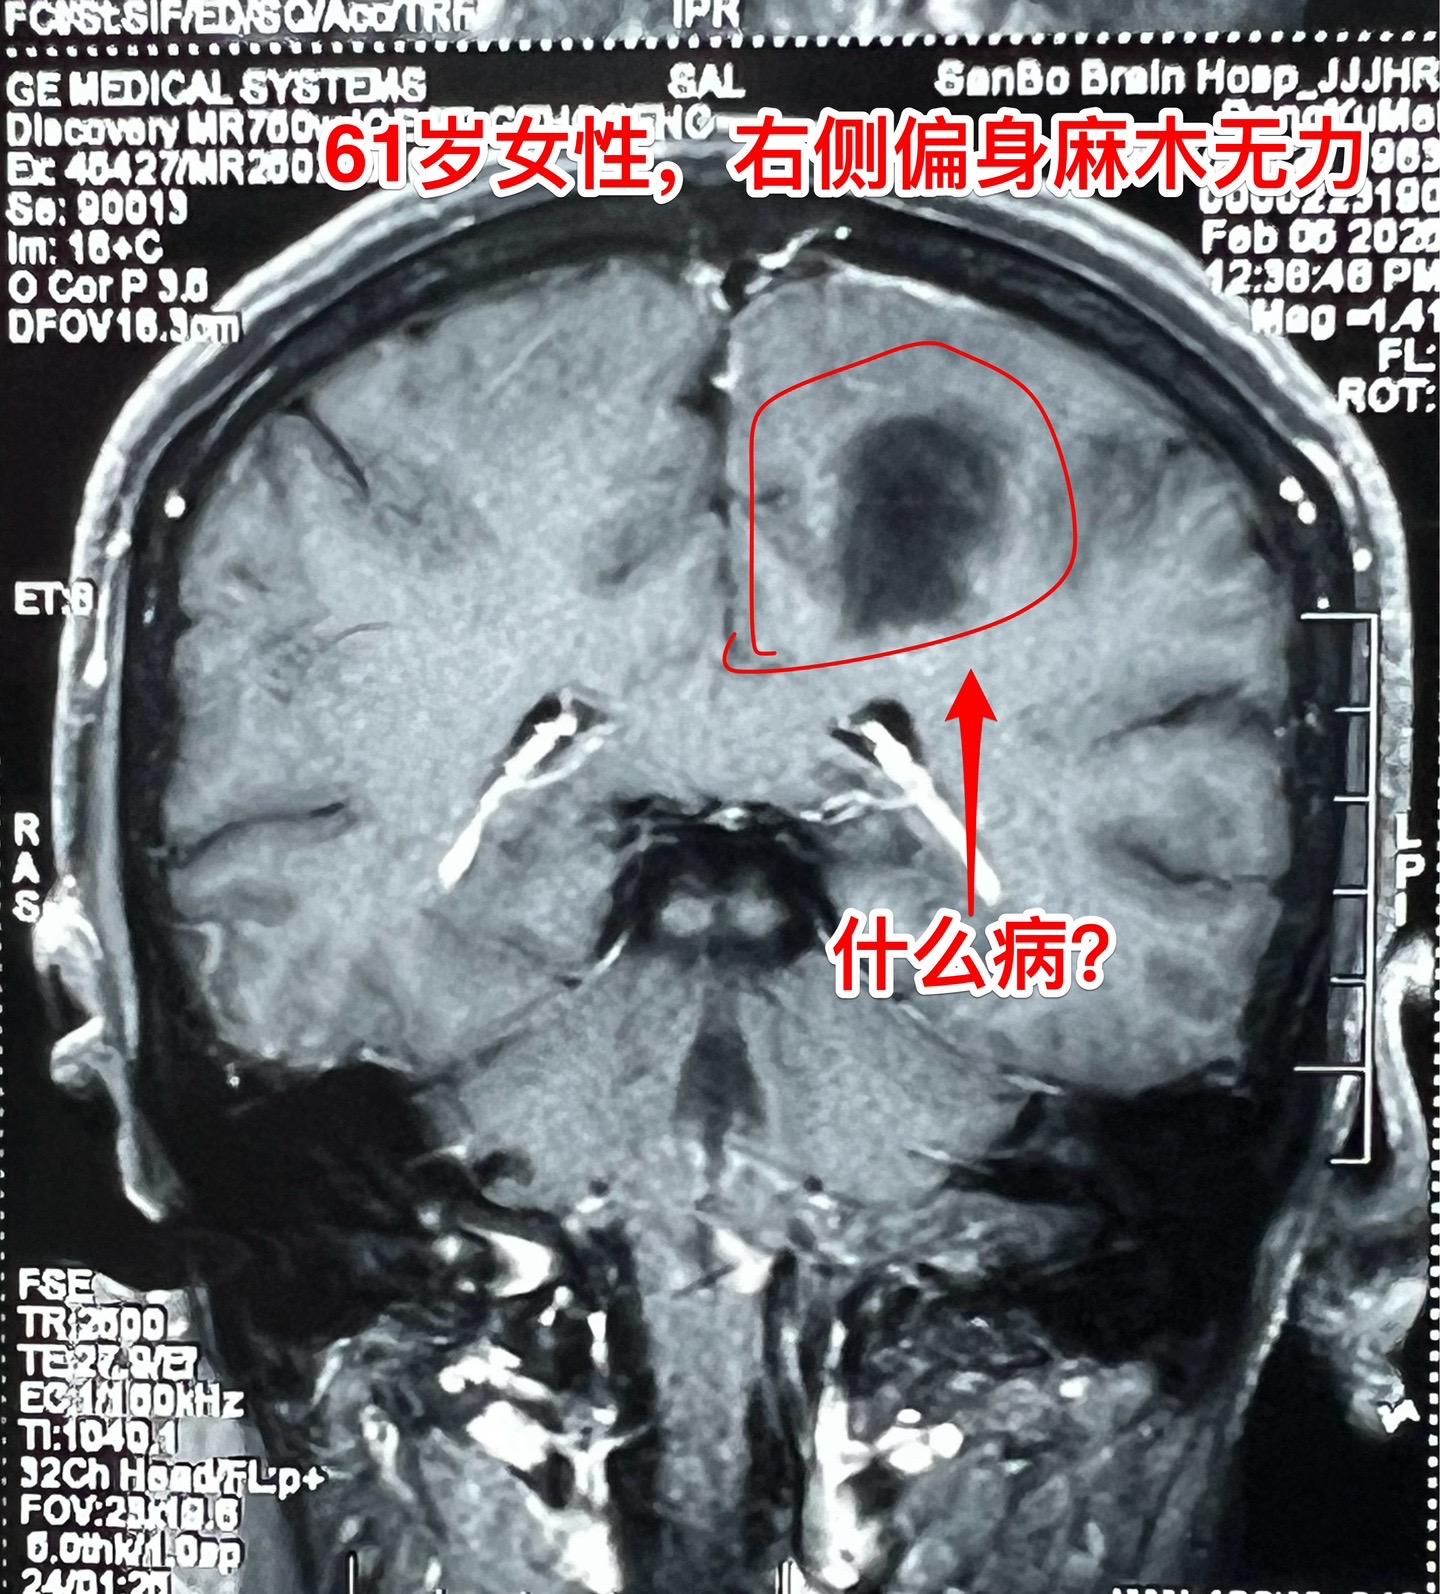

疾病多种多样,鉴别诊断不易!近几年人工智能AI发展迅猛,成果惊人! 听说有AI医院! 医生和病人都会提问:AI能取代医生看病吗? 今天介绍一个病人,61岁女性,因右侧偏身麻木无力来看病。CT和磁共振显示左侧中央区有个病灶,见图。怀疑是胶质瘤? 病人的症状越来越严重,正月初九住院后行走困难,而且右手手指难以张开,术前和病人家属充分交流、沟通,这个位置属于中央区,手术后很可能症状会加重。患者的两个儿子均想积极治疗。住院后两天做了手术。手术过程中发现